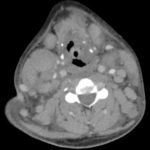

Hodgkin’s lymphoma is a neoplastic proliferation of Reed Sternberg cells and inflammatory cells within the lymphatic system. Common symptoms associated with Hodgkin’s Lymphoma include pronounced lymphadenopathy, fever, polynuclear leukocytosis, and anemia.1,2 This case study presents a unique case where an adult patient with nodular sclerosing Hodgkin’s lymphoma (NSHL) presents with rapidly progressing dyspnea due to tracheal airway narrowing. CT results showed pathological lymph nodes in bilateral cervical stations, subclavian images and within the mediastinum, concerning for lymphoproliferative disease. Otolaryngology was consulted for a possible tracheostomy; however, an awake fiberoptic intubation was suggested and subsequently performed instead. This case demonstrates the importance of immediate intervention to prevent airway loss in an atypical presentation of NSHL.